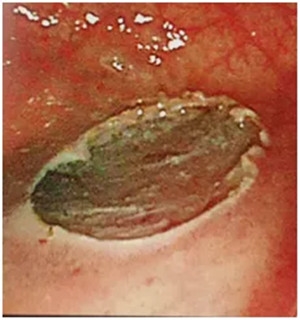

手术完后是这样的

最后组织夹封闭完创面是这个样子的

病人需要卧床48小时后逐步恢复流质-半流质-正常饮食;后期术后病理会出个结合免疫组化的大病理。